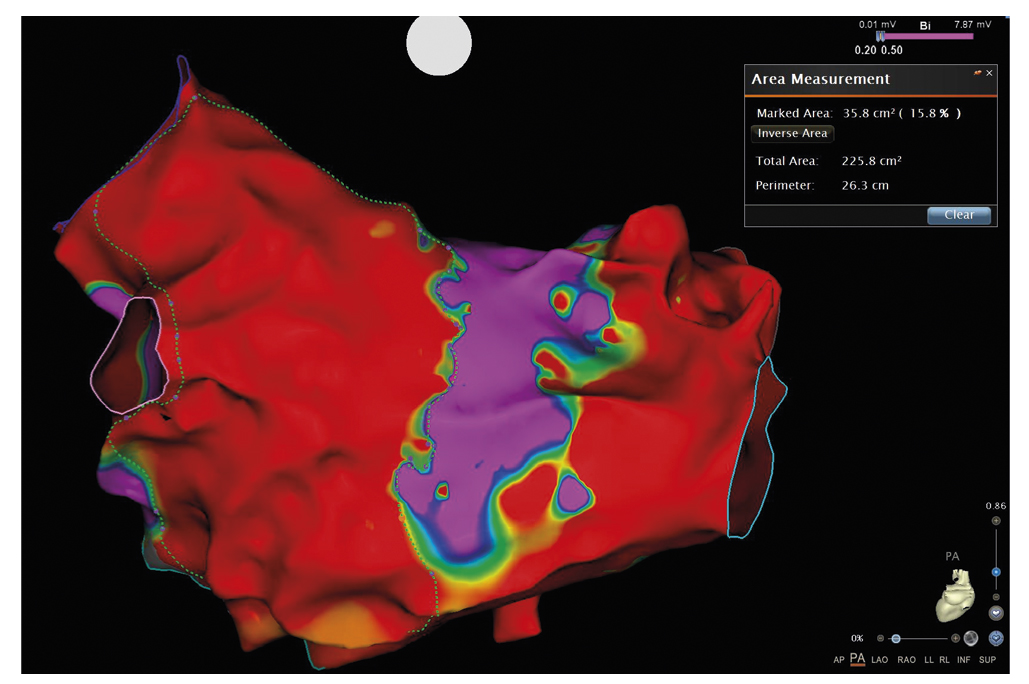

Выполнена транссептальная пункция; в левом предсердии позиционирован катетер для высокоплотного картирования PentaRey (Biosense Webster, США); выполнена анатомическая реконструкция ЛП с построением активационной и вольтажной карт. Электроанатомическая карта ЛП содержит 2457 аннотированных точек картирования, расстояние между точками 1–3 мм. При анализе высокоплотной вольтажной карты отмечаются распространенные зоны низкоамплитудной активности, занимающие всю антральную часть ЛП (рис. 2). Выполнен подсчет площади низкоамплитудных зон с использованием инструмента Area Measurement, определен процент от общей площади ЛП. Выявлены 42,1% областей низкоамплитудной активности в ЛП.

Рис. 2. Высокоплотная вольтажная карта левого предсердия, построенная с помощью системы навигационного картирования Carto 3. Красные области — участки с амплитудой эндокардиального сигнала менее 0,2 мВ, фиолетовые — с амплитудой эндокардиального сигнала более 0,5 мВ. / Fig. 2. A high-density voltage map of the left atrium, built using the Carto 3 navigation mapping system. Red areas correspond to the endocardial signal amplitude lower than 0.2 mV, purple areas — to the amplitude higher than 0.5 mV.